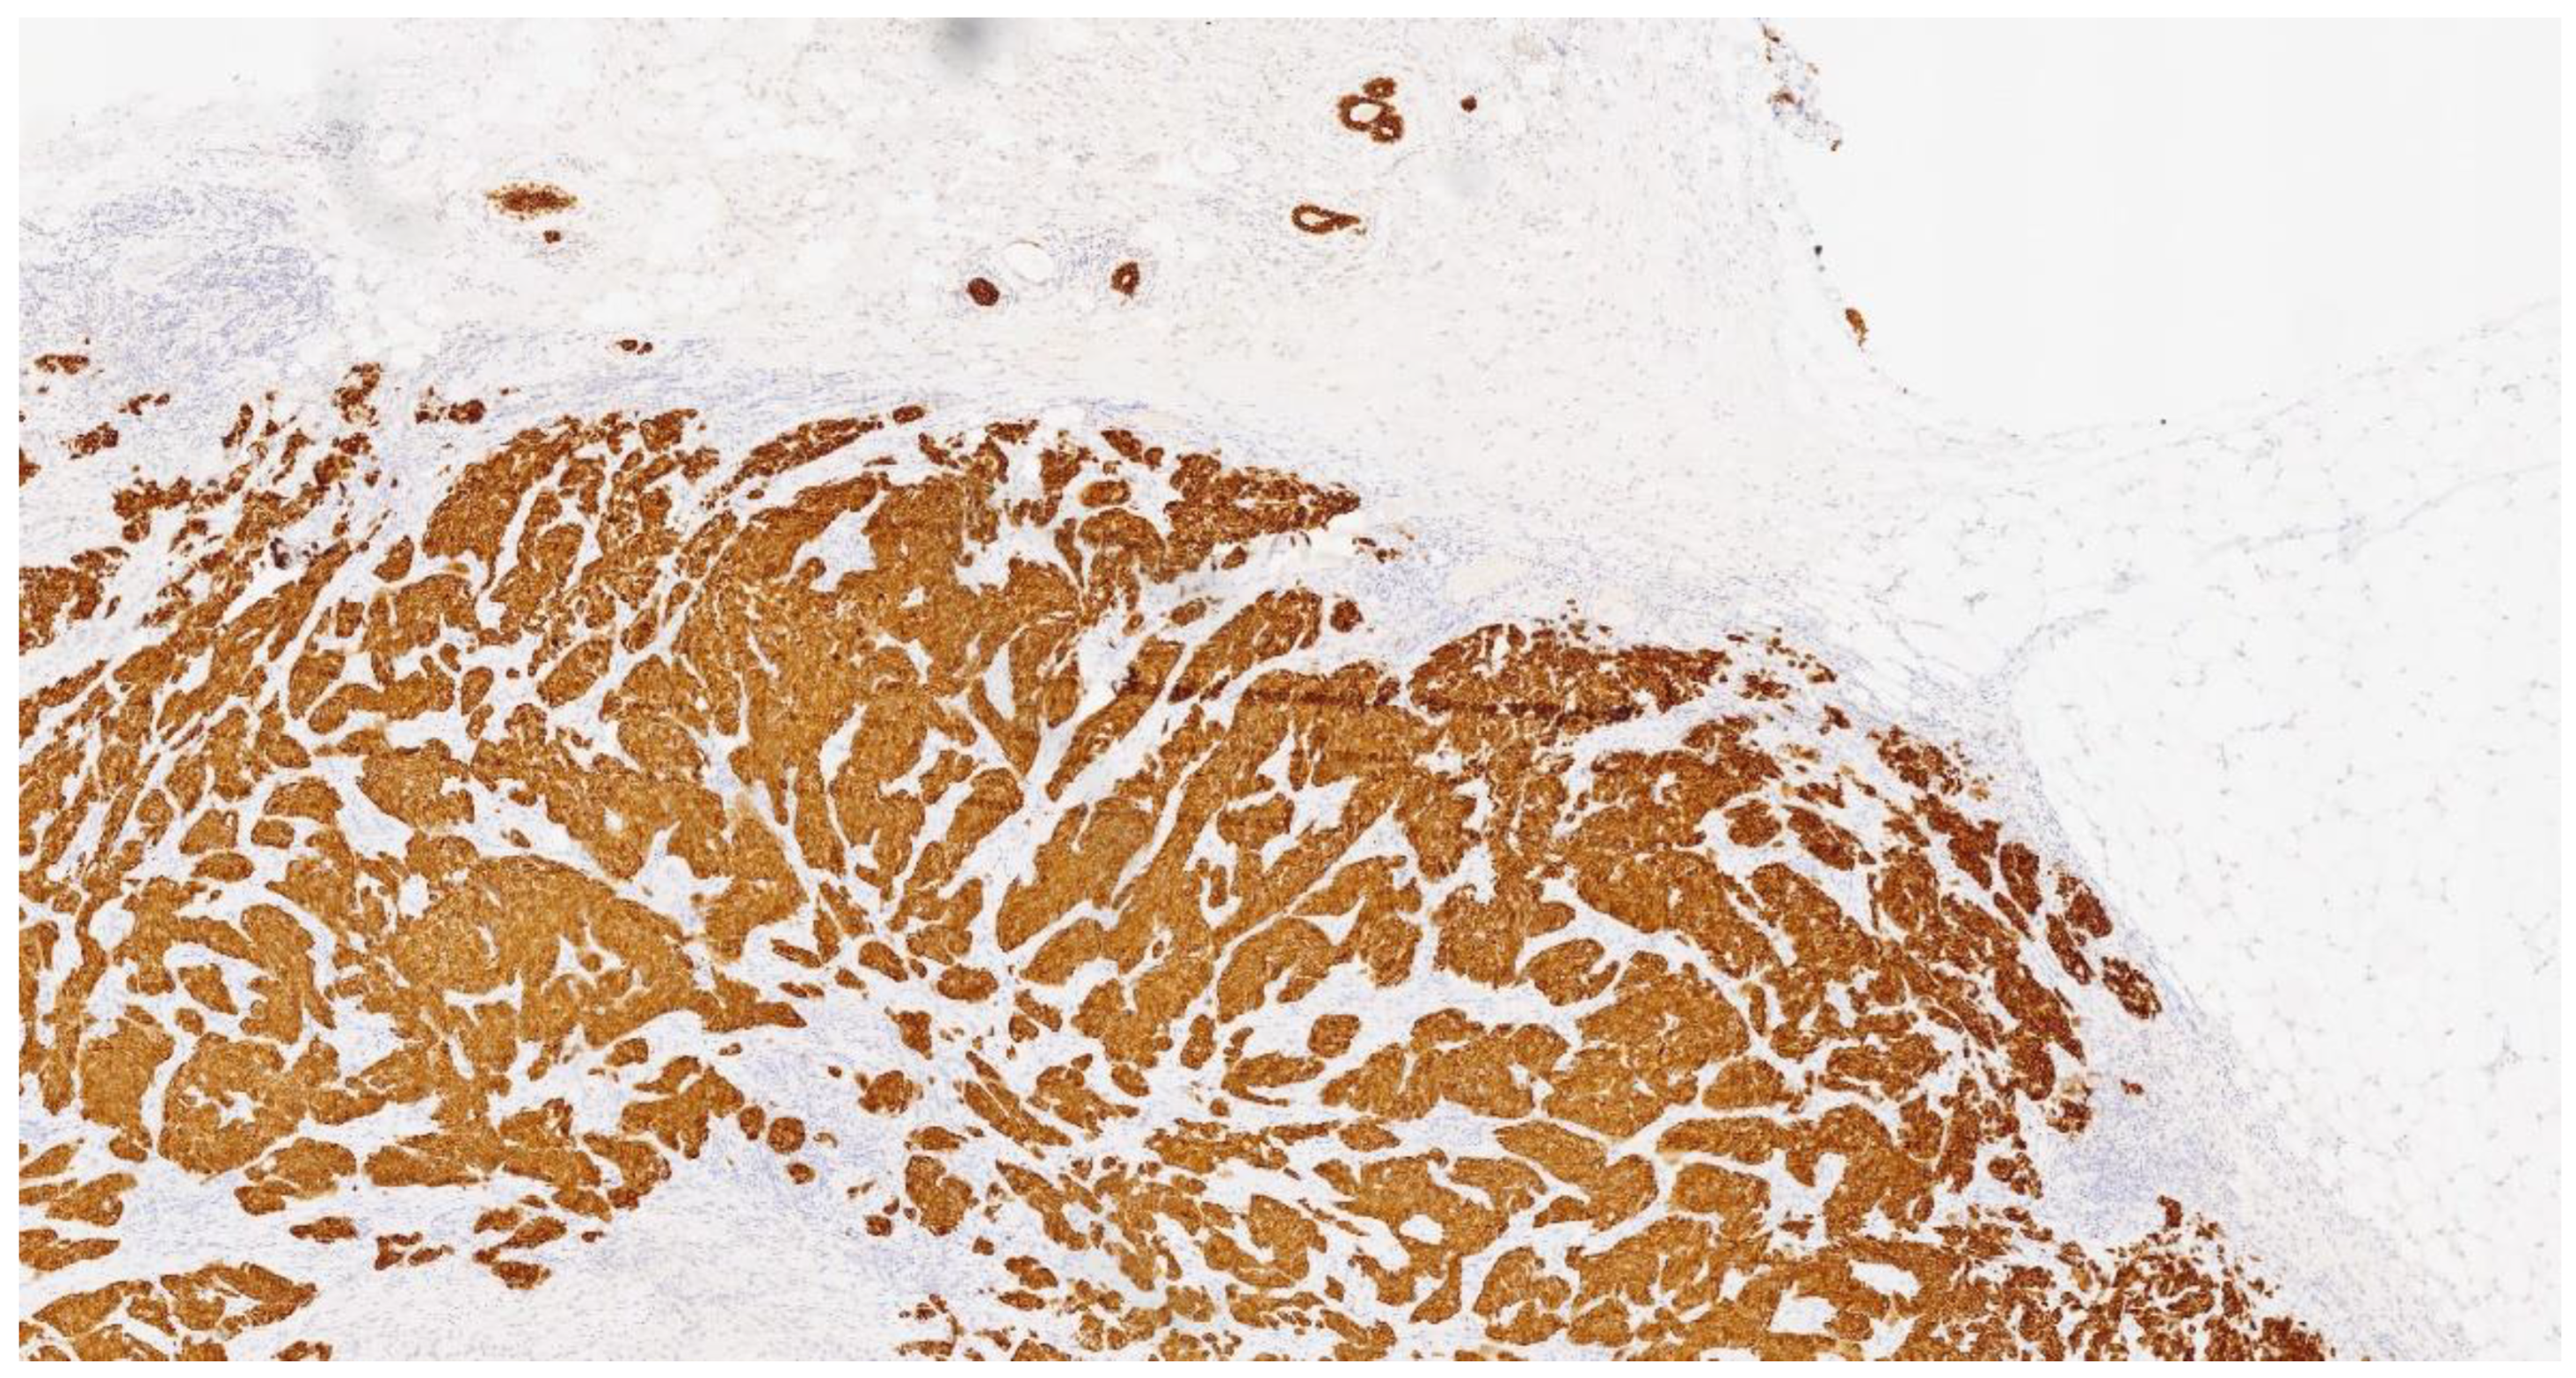

2. Case Presentation